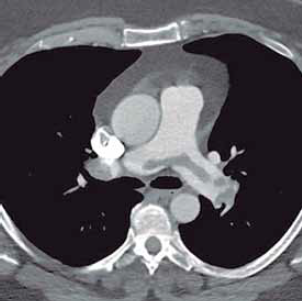

Considere um paciente hemodinamicamente estável com a seguinte tomografia de tórax.

(Arquivo pessoal; imagem usada com autorização)

Quanto ao manuseio terapêutico, a conduta inicial correta é